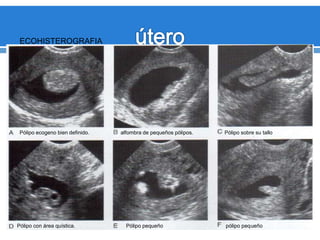

Pólipos

endometriales

Engrosamiento

endometrial

ecógeno

inespecifico

(Difusos o Focales).

Masas

ecógenICASas

focales, redondas.

ECOHISTEROGRAFIA

Pólipo ecogeno bien definido. alfombra de pequeños pólipos. Pólipo sobre su tallo

Pólipo con área quística. Pólipo pequeño pólipo pequeño